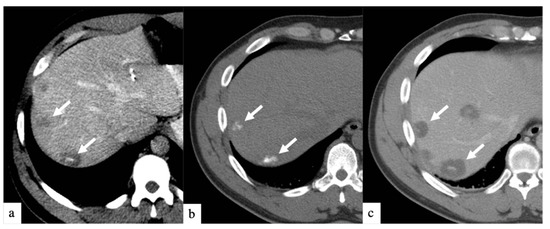

3. Results